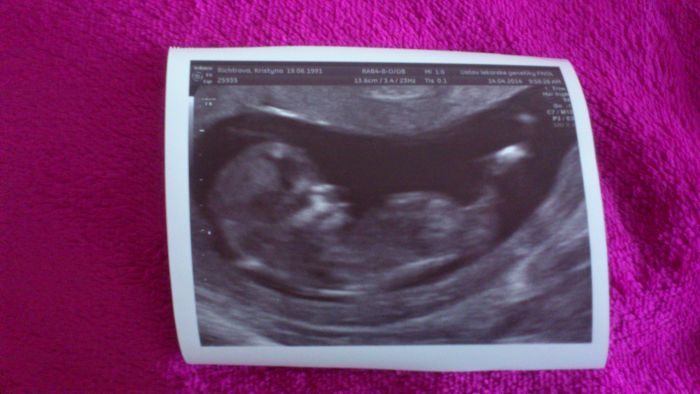

Ahojte holky.. Konečně jsem se po stěhování dostala na internet.. Zápřah teda slušný, doma je jak po výbuchu, ale jsem přestěhovaní..Jinak dneska jsem byla na screeningu, prohlídka v pořádku, slyšela jsem srdíčko Dostala jsem fotečku, ale miminko sebou házelo a nešlo moc vyfotit.. Pohlaví mi neřekla, že je ještě brzy a posunula mě o pár dní dozadu,jsem prý 12tt (měla jsem být 13tt).. Takže tak

Tynus, to je krásná fotečka, náhodou, na to, že s sebou mimi házelo je to paráda, jak je miminko už veliké? Když se podívám do mobilu na svou první fotečku z ultrazvuku tak tam není skoro nic vidět...jak rychle to mimi roste, zírám....

Cami asi 5,5 cm...